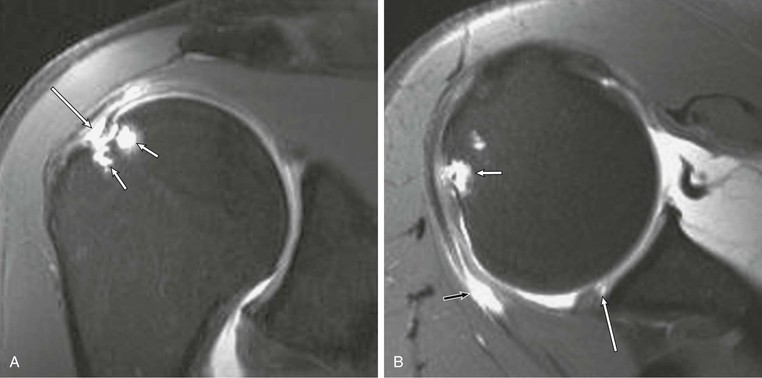

An intramuscular cyst within the rotator cuff (Fig. 44-27, A and B) has been described as a finding associated with small full-thickness tears or partial-thickness articular-sided tears of the rotator cuff.114 Intramuscular cysts are similar to paralabral cysts of the shoulder or meniscal cysts of the knee. Fluid leaks through a defect in the cuff and tracks in a delaminating fashion along the fibers of the tendon, resulting in a fluid collection contained within either the muscle or fascia of the rotator cuff. These cysts have been reported in the supraspinatus, infraspinatus, and subscapularis muscles and appear as oval lobulated collections of low signal intensity on T1-weighted images and high signal intensity on T2-weighted images. Identification of an intramuscular cyst of the rotator cuff should prompt a thorough search for a small associated cuff tear.

Denervation of a rotator cuff muscle can result from either a compressive neuropathy or an acute traumatic injury of a nerve. Compressive neuropathies most commonly result from a paralabral cyst associated with a labral tear, but they can also be caused by fractures or other masses in the area of the shoulder (see Fig. 44-23, A and C). Paralabral cysts (Fig. 44-28) most commonly arise in association with a SLAP tear or a posterior labral tear. These cysts may extend into either the suprascapular notch or the spinoglenoid notch and can result in entrapment of the suprascapular nerve, which innervates the supraspinatus and infraspinatus muscles.115 Paralabral cysts arising from an anteroinferior labral tear are less common, but they may compress the axillary nerve as it traverses the quadrilateral space.116 Compression of the axillary nerve can also result from adhesive bands in the quadrilateral space in athletes, such as pitchers, who participate in repetitive overhead activities.117 The axillary nerve innervates both the teres minor and deltoid muscles. Anterior dislocation can result in a stretching injury of the axillary nerve and give rise to a temporary or permanent denervation of the teres minor and deltoid muscles and can occasionally mimic a rotator cuff tear on clinical examination in a person with previous anterior dislocation. Denervation atrophy initially results in edema of the affected muscles and over time will progress to an irreversible fatty replacement. On MRI, acute denervation edema appears as a high T2-weighted signal within the affected muscle and is associated with reversible muscle atrophy (Fig. 44-29). The more chronic and irreversible form of fatty atrophy appears as decreased muscle bulk and bright streaks (representing the fat) within the muscles on T1-weighted images (see Fig. 44-23).